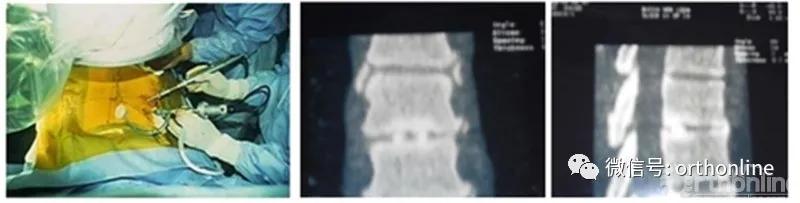

图5.

图5. Osman的单侧双通道内镜手术图及自体骨融合。引自Osman SG, Schwartz JA, Marsolais EB. Arthroscopic discectomy and interbody fusion of the thoracic spine: A report of ipsilateral 2-portal approach. Int J Spine Surg 2012; 6:103-109.